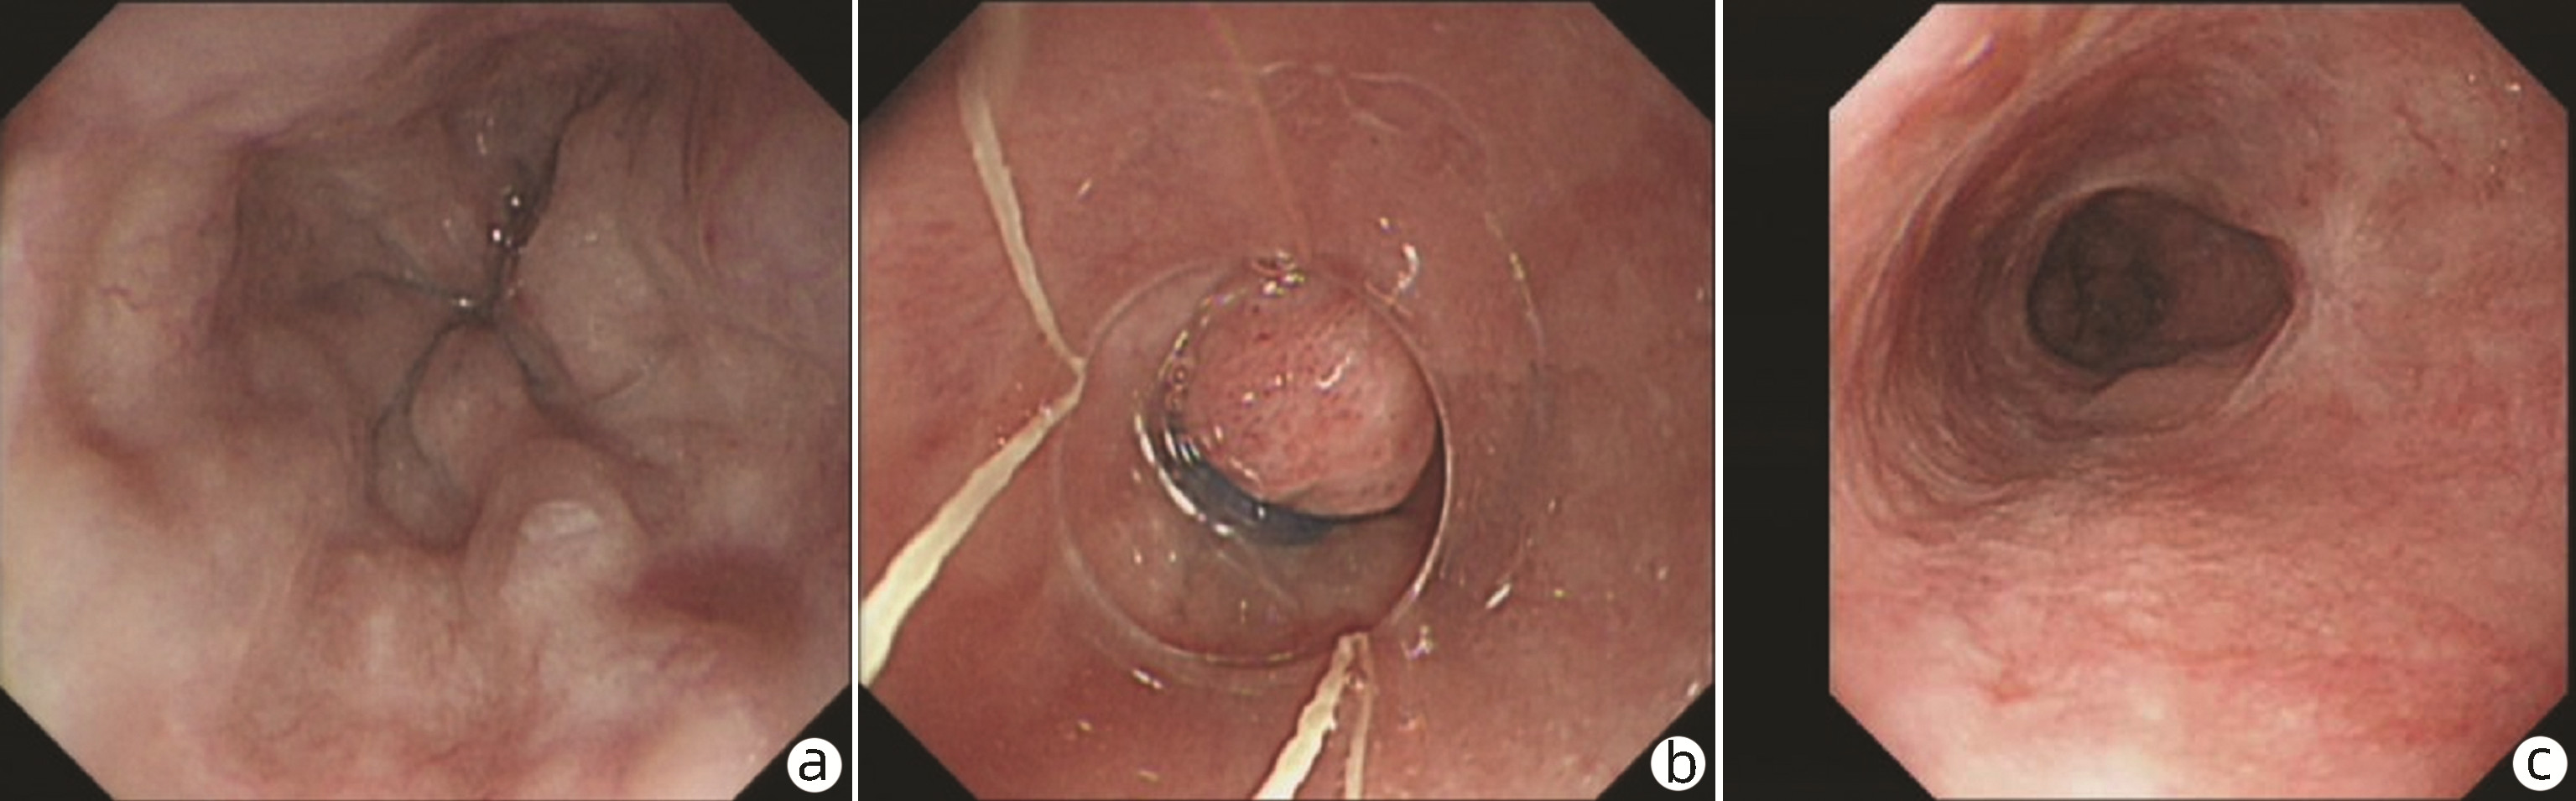

Endoscopic sequential ligation for treatment of esophageal and gastric varices with duodenal varices: A case report

Hao WEN, Zhaohui HE, Tong JIANG, Guoqing SHI

2023, 39(3): 637-639. DOI: 10.3969/j.issn.1001-5256.2023.03.024

Abstract(837) HTML (263) PDF (2676KB)(95)

Abstract: